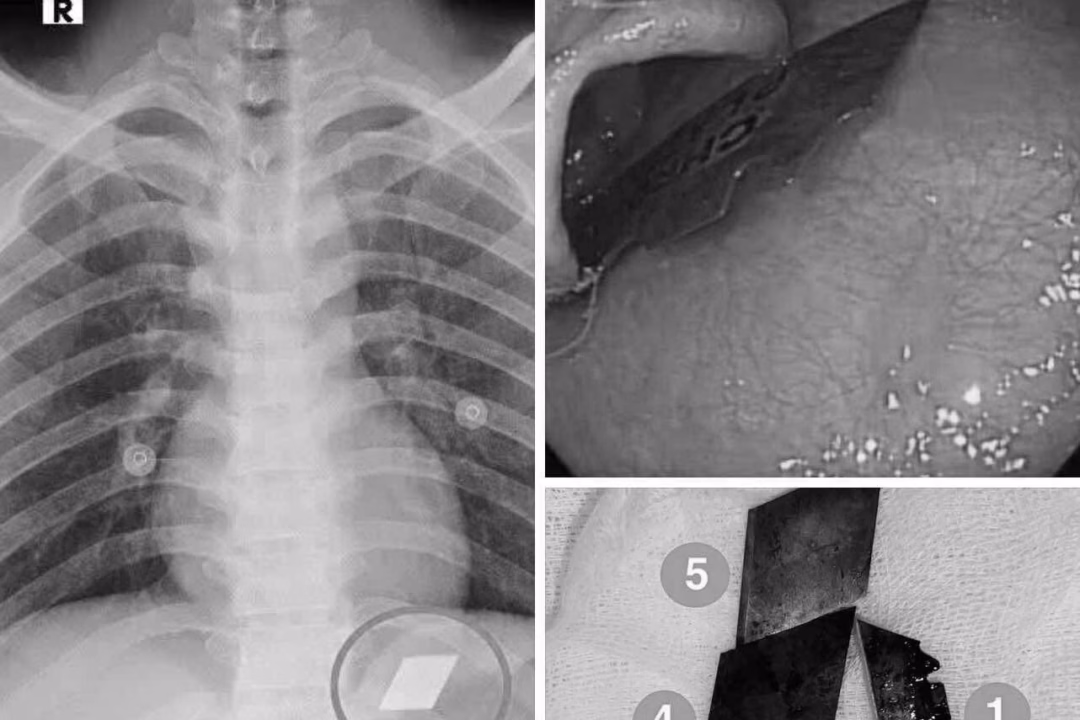

Nam thanh niên 26 tuổi nuốt nhiều mảnh dao rọc giấy và dao lam, được đưa vào Khoa Hồi sức cấp cứu – Bệnh viện Đa khoa Bình Dương. Sau khi chụp X-quang, bác sĩ phát hiện các dị vật cản quang trong dạ dày và tiến hành nội soi cấp cứu, gắp thành công 4 lưỡi dao rọc giấy và một phần lưỡi dao lam. Hiện, bệnh nhân đã ổn định và được xuất viện an toàn.